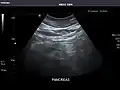

Kidneys: Right and left kidneys measure 11.5 cm and 12 cm in length respectively. No hydronephrosis. Small left lower pole kidney cyst.

Right kidney -